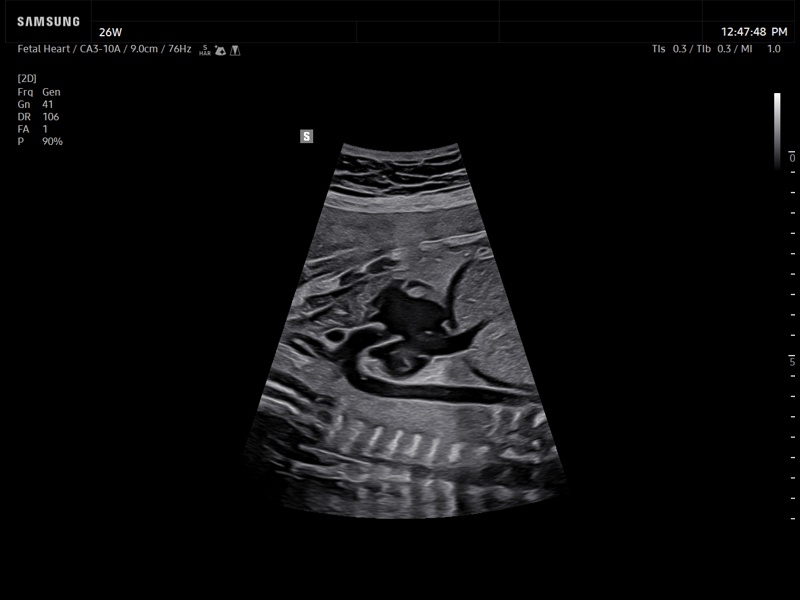

[RU] Ultrasound image №937: Fetal heart using Luminant™ (highlighting the boundaries of structures). 26 weeks of gestation, convex probe 3-10 MHz.

Echogramm was received by ultrasound scanner Z20 (new model).